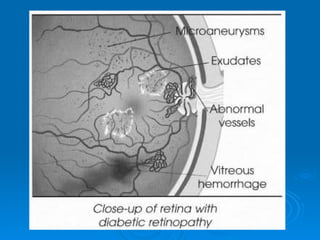

Diabetic Retinopathy

Ø microangiopathy

Ø affects pre-capillary arterioles, capillaries

and post-capillary venules

Ø features of:

l   microvascular occlusion

l   leakage

clinically, can be divided into:

l   background DR (nonproliferative)

l   preproliferative DR

l   proliferative DR

Proliferative Diabetic Retinopathy

Ø   more likely to become

symptomatic than early

NPDR

Ø   may have decreased

vision, sudden vision loss,

floaters, cobwebs, flashes,

dull eye ache

Ø   PDR can also affect visual

function by affecting the

macula with resulting

macular ischemia and/or

edema

Proliferative DR

Ø   affects 5-10% of the diabetic population

Ø   neovascularization is the hallmark

l NVD: neovascularization of the disc

l NVE: neovascularization elsewhere

Ø   new vessels are not only extremely fragile

(intraretinal or vitreous hemorrhage), but

often associated with fibrous proliferation,

leading to an increased risk of tractional retinal

detachment